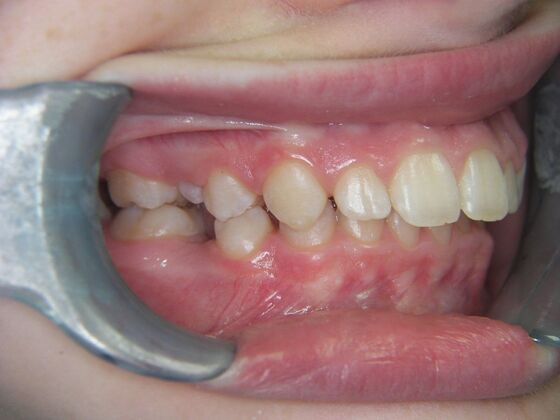

Orthodontics: Case 2

Patient is 9 years old and presents with 100% overbite and blocked out upper and lower lateral incisors. Both upper central incisors are palatally inclined causing a lack of space available for most anterior teeth. Advised her parents that she needs Phase I Interceptive Orthodontic treatment to provide room for all upper and lower front teeth. Phase I treatment was begun and finished, then began Phase II treatment shortly thereafter to finalize case. Removable retainer were fabricated for retention.